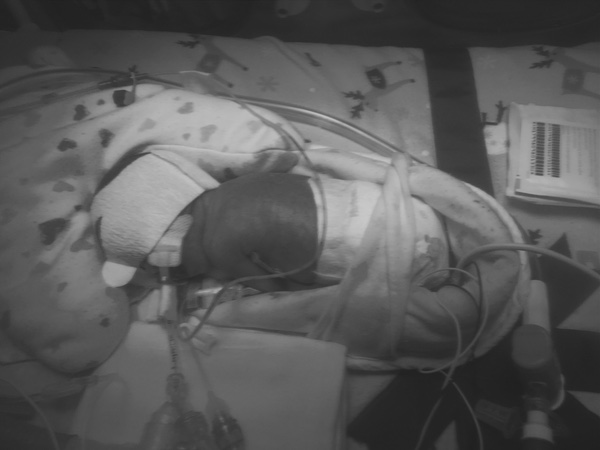

A start to a long bumpy road that we weren't prepared for, Kazlyn will be spending at least the next 13 weeks In the NICU. Her lungs aren't mature, intibated with periods of apnea, a ventilator assist her with breathing. Constant changes are being made with her fluids, feeding, and ventilator. Our biggest worry; the heart echo and cerebral ultrasound came back and everything looks good. Tolerating only a milliter of breast milk over an hour, everyday she becomes stronger. Her eyes are still fused and we are anxiously awaiting the day our eyes meet.